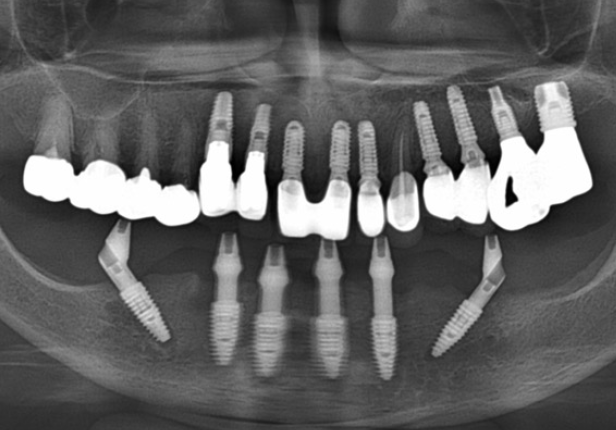

Panorâmica pós-cirurgia

caso de estudo

Panorâmica Final da Coroa

Ponte ARi caso de estudo